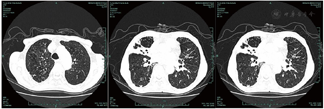

共317例TOPD患者完成影像学检查。TOPD患者肺部CT显示多处钙化结节等结核瘢痕,部分患者存在一定程度的肺气肿和支气管扩张征象,见图1,图2,图3。TOPD患者左肺上、舌、下叶的结核瘢痕阳性分别为176例(55.5%)、120例(37.9%)和126例(39.7%),右肺上、中、下叶的结核瘢痕阳性分别为215例(67.8%)、142例(44.8%)、168例(52.9%);左肺的支气管扩张征象主要集中在左肺舌叶,右肺主要位于中叶、下叶;肺气肿在双肺间分布较为均衡,见图4。

注:患者男,78岁,双肺见多发薄壁空腔影,右肺上叶尖段见扩张支气管影;右肺中叶见实变影,部分钙化,其内见充气支气管征象;右肺下叶可见散在钙化结节、索条影,可见充气支气管征、肺气肿